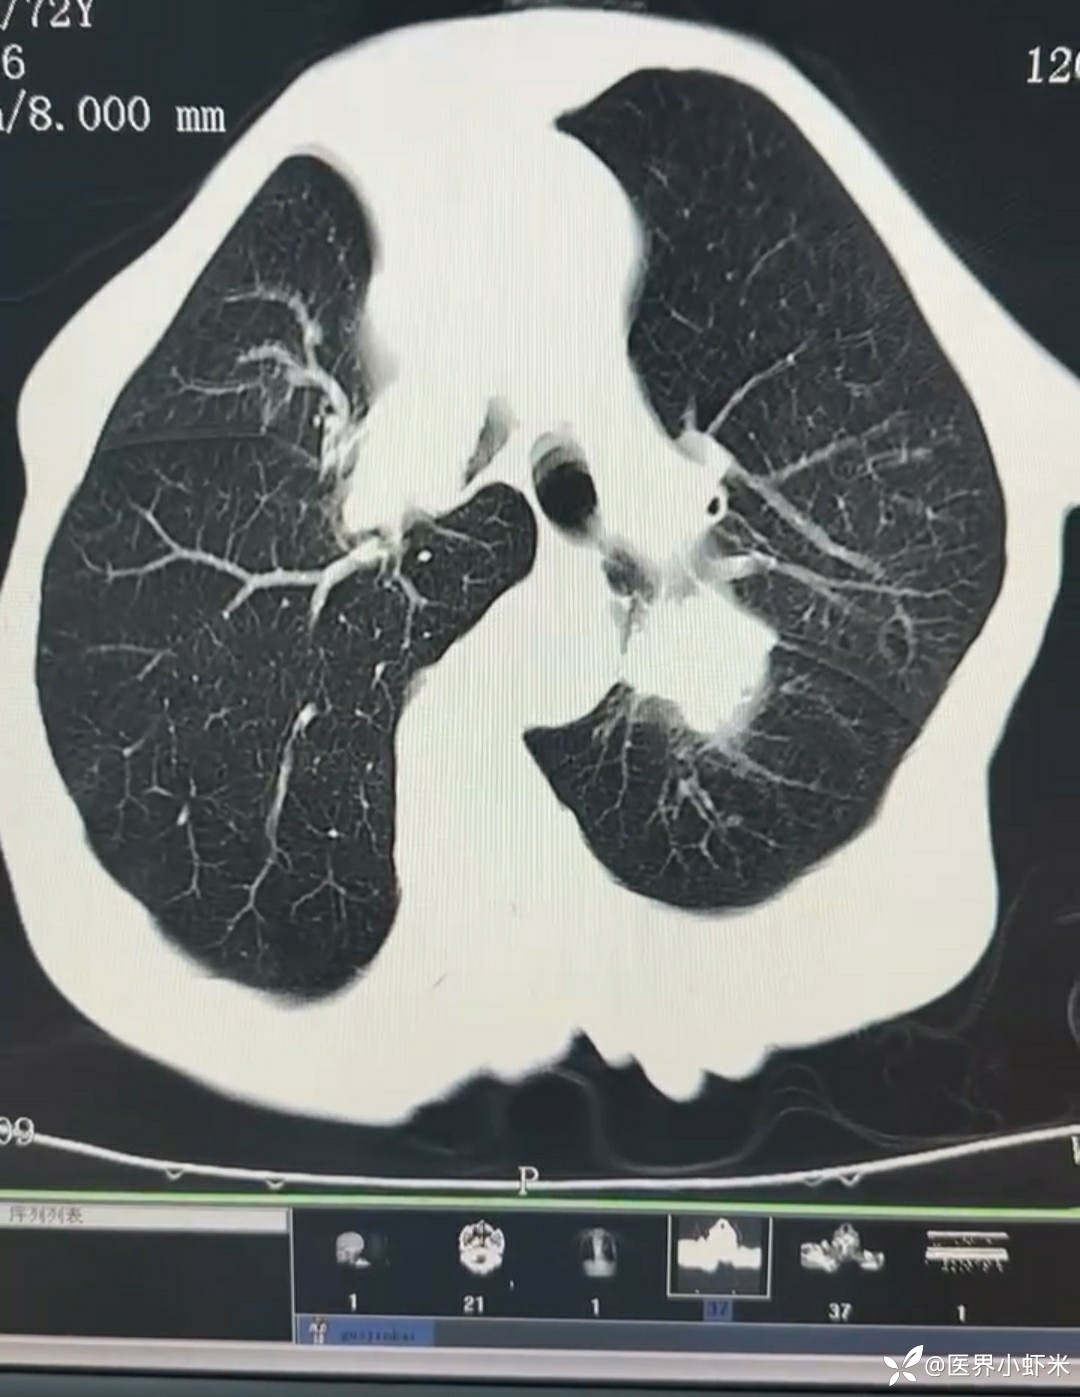

目前考虑:1.中央型肺癌伴2.肝继发恶性肿瘤?2.左丘脑继发恶性肿瘤?3.左丘脑出血?4.肾功能不全5.肝功能异常6右肾萎缩7.肺部感染8.慢性阻塞性肺病7.高血压3级(极高危)。